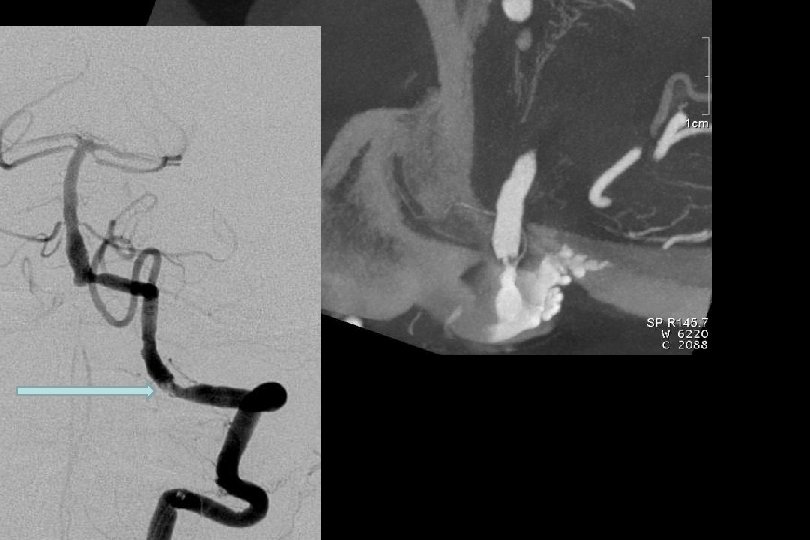

Atherosklerotik plak morfolojisi Dyna BT Anjiyografi gösterilebilir ve stent tipi buna göre seçilebilir.

11 yıl kontrol MR/MRA

2. yıl kontrol